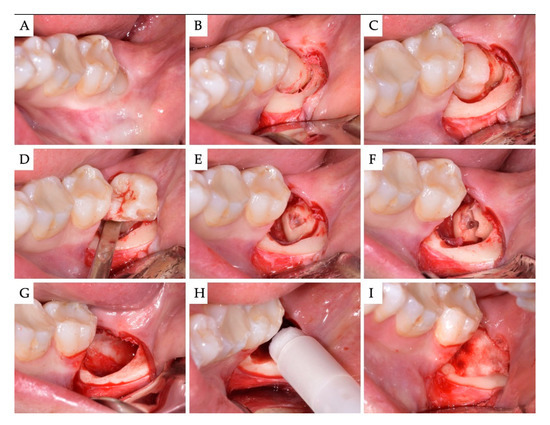

2. Materials and Methods